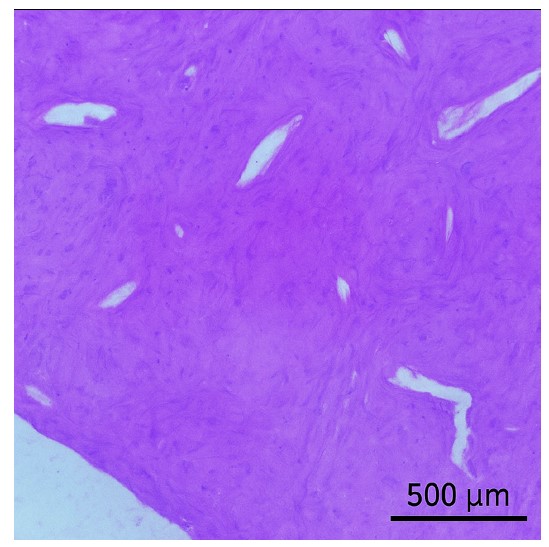

Histological examination revealed complete replacement of normal bone structure with a sclerotic osseous mass, including detectable Haversian systems. The diagnosis of idiopathic osteosclerosis was confirmed based on clinical, radiological, and histological findings (Fig. 2).

Histological examination of the radiopaque lesion confirming the diagnosis of osteosclerosis.

Histological examination of the radiopaque lesion after removing the lesion and the dental implant.

The first case demonstrated successful osseointegration despite the presence of IO, with favorable stability values observed during follow-up examinations. This outcome suggests that dense sclerotic bone may not necessarily contraindicate implant placement, provided appropriate surgical techniques are employed [20, 21]. The high insertion torque achieved during placement and subsequent increase in resonance frequency analysis values indicate that the mechanical properties of sclerotic bone can, in some cases, contribute to favorable primary stability [21, 22]. However, the biological behavior of such bone remains questionable, as the reduced vascularity typical of sclerotic lesions might theoretically compromise the healing response [23-25]. The histological findings in this case, showing replacement of normal bone architecture with dense lamellar bone containing Haversian systems, confirm the diagnosis while highlighting the structural differences from normal alveolar bone [22, 26].

The first case demonstrated successful osseointegration despite the presence of IO, with favorable stability values observed during follow-up examinations. This outcome suggests that dense sclerotic bone may not necessarily contraindicate implant placement, provided appropriate surgical techniques are employed [20, 21]. The high insertion torque achieved during placement and subsequent increase in resonance frequency analysis values indicate that the mechanical properties of sclerotic bone can, in some cases, contribute to favorable primary stability [21, 22]. However, the biological behavior of such bone remains questionable, as the reduced vascularity typical of sclerotic lesions might theoretically compromise the healing response [22, 26, 27]. The histological findings in this case, showing replacement of normal bone architecture with dense lamellar bone containing Haversian systems, confirm the diagnosis while highlighting the structural differences from normal alveolar bone [22, 26].